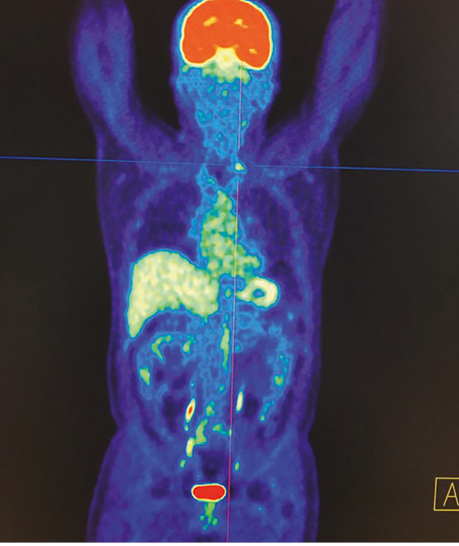

В якості ілюстрації наводимо клінічні випадки виконання ПЕТ / КТ з 18F-ФДГ у хворих з йод-негативними вогнищами ДРЩЗ з метою діагностики та постлікувального моніторингу.

Хворий А., папілярний рак щитоподібної залози, 4 курси РЙТ, відсутність накопичення 131I-NaI на постлікувальному скані після 3-го курсу. За даними УЗД та КТ обстеження — підозра на можливі вогнища в зоні шиї та легень. Хворому назначено ПЕТ / КТ з 18F-ФДГ (рис. 4, 5).

Рис. 4. ПЕТ / КТ з 18F-ФДГ. Візуалізується вогнище гіперфіксації 18F-ФДГ в надключичній зоні справа

Рис. 5. ПЕТ / КТ з 18F-ФДГ. Візуалізується вогнище в зоні шиї

За даними ПЕТ / КТ з 18F-ФДГ у цього пацієнта підтверджено наявність вогнища гіперфіксації РФП в зоні шиї, водночас не виявлено ознак пролонгації процесу в легенях. Вірогідно, ідентифіковані вогнища за даними КТ відповідають фіброзним змінам після перенесених запальних процесів.

Після проведення діагностичного обстеження хворому призначено таргетну терапію препаратом Нексавар® згідно з протоколом лікування.

Діагностичне сканування з 18F-ФДГ допомогло виявити зниження функціональної активності вогнища в зоні шиї (SUV — 6,9–4,2). Зменшення розміру вогнища не відмічалося (рис. 6).

Рис. 6. ПЕТ / КТ з 18F-ФДГ. Вогнище гіперфіксації 18F-ФДГ у надключичній зоні справа, метаболічне зображення після проведення таргетної терапії